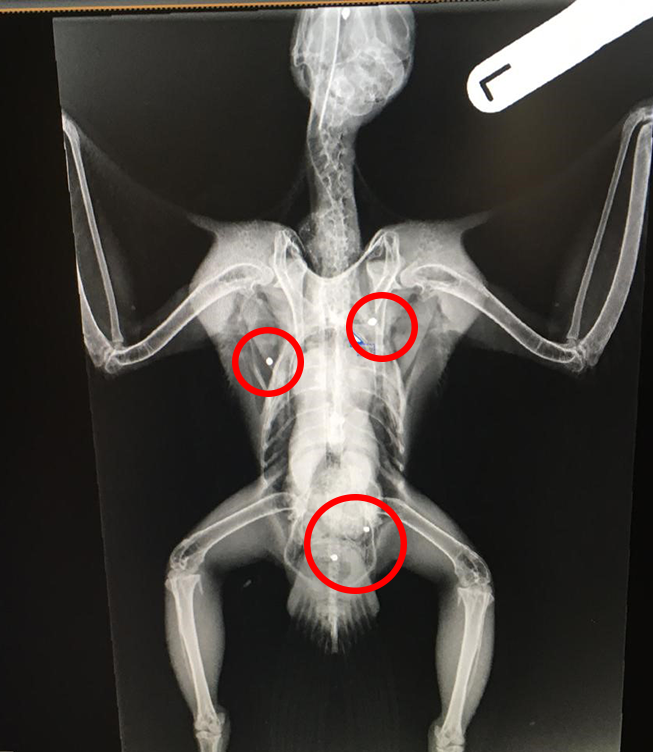

The peregrine was rescued and x-rayed by a local falconry specialist vet, Mark Naguib, who found a number of shotgun pellets throughout the bird’s body. The peregrine is ringed by the British Ornithology Trust so was able to be traced back to being released as a chick near Newark eight years ago.

“We are appalled at this deliberate and illegal attack on a protected peregrine falcon. The bird was riddled with shot, including one piece lodged in its head. Incredibly, it is still alive but it’s touch and go.